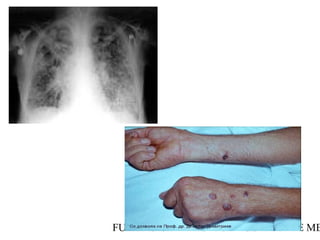

Ánthrax inhalatorio

• No es exactamente una neumonía: predominan la

linfadenitis hemorrágica y mediastinitis, 25%

presentaron hemorragia pulmonar.

• Enfermedad bifásica: 1-6 días de incubación, con

fiebre, mialgias, tos seca,malestar general y dolor

torácico y abdominal.

• En 3 días progresa a fiebre alta, disnea, diaforesis,

y cianosis. Estridor en aquellos con obstrucción

extrínseca de la tráquea por edema. Edema

subcutáneo en tórax y cuello. 50% se complican

con meningitis. En 24-36 horas shock, hipotermia.